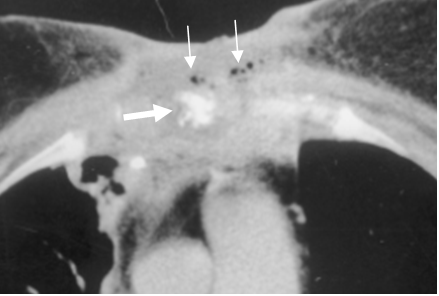

Fig 36. Osteomielitis del esternón.

TAC axial. Osteolisis del esternón (Flecha gruesa), con cambios inflamatorios en los tejidos blandos vecinos. Existen burbujas de aire asociadas. (Flechas delgadas).